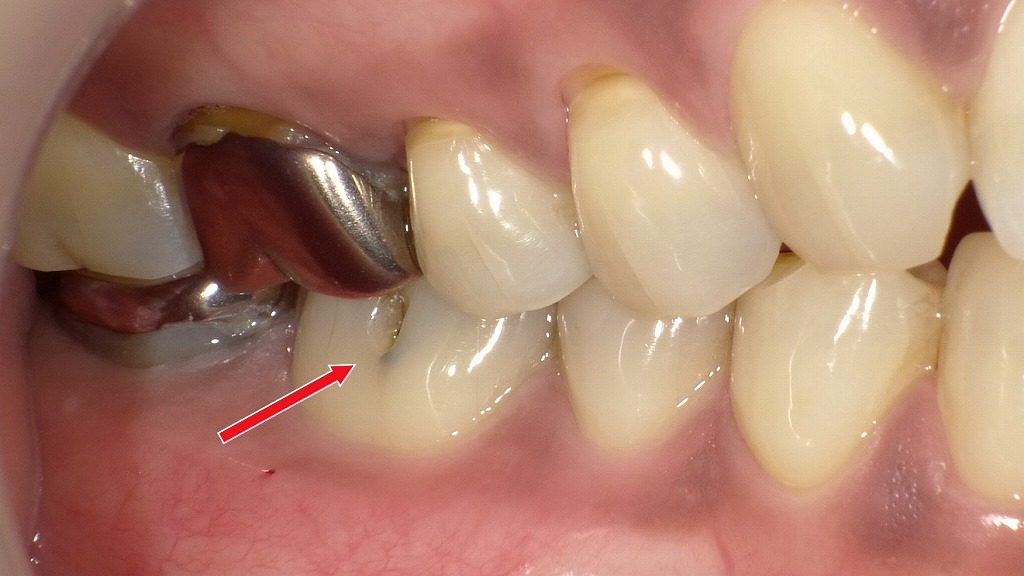

歯石の黒色化

歯の根元や歯と歯の間に付着した歯石が、唾液中の成分や細菌の代謝物、タバコのヤニなどと反応して黒く変色した状態を「縁下歯石(黒色歯石)」と呼びます。

黒色歯石は、通常の白っぽい歯石よりも硬くて強固に付着するため、日常のブラッシングでは取り除くことができません。

このタイプの歯石が見られる場合、

- 歯周病が進行しているサインであることが多い

- 歯肉の炎症や出血を引き起こしやすい

- 歯周ポケットの内部にまで及ぶことがある

といった特徴があります。

除去するには、歯科医院で行うスケーリングやルートプレーニングが必要です。黒色歯石を放置すると細菌の温床となり、歯周病が悪化する恐れがあるため、早めのケアが重要です。